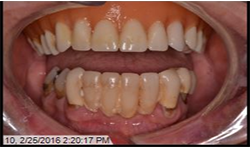

At a second appointment, four Bicon SHORT implants, three 4 x 6 mm and one 3.5 x 8 mm were placed in the mandibular arch (Figs. 9, 10). After normal healing time, both the maxillary and mandibular arches were fitted with a fixed hybrid prosthesis fabricated from a TRINIA substructure and Ceramage denture teeth. The patient was happy with the fit, function and comfort (Fig. 11).

Fig.11

The previous case studies demonstrate difficult restorative cases made easier with the products and techniques now available. Using Bicon SHORT Implants and TRINIA metal-free substructures in our predoctoral clinics has become a successful combination for completely edentulous patients.

TRINIA telescopic prosthetic material has revolutionized the ability for our predoctoral students and general practitioners to be successful with all-on-four semi-removable prosthetic appliances. This combination is a great option for patients who do not want any metal prostheses in their mouth, but want a semi-permanent restoration when edentulous. Many patients comment that their new fixed-hybrid feels very similar to their original teeth because they do not have the additional weight of a metal framework.12

Using the Bicon implant system and telescoping crown abutments, the TRINIA base is a perfect match. Within the system of four implant copings, two are passive and two are retentive. The patients report the restorations feel natural, lightweight and chew and function similar to their natural dentition.

Patient satisfaction has been noted to be highly positive to the use of these two materials as a system. Patients especially appreciate the similar density to bone, so there is a weightless feeling to the prosthesis similar to natural dentition.